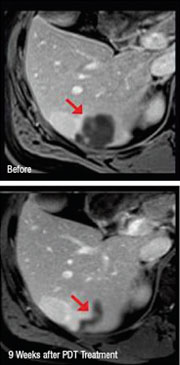

Patient showing improvement of liver cancer following NexGen PDT